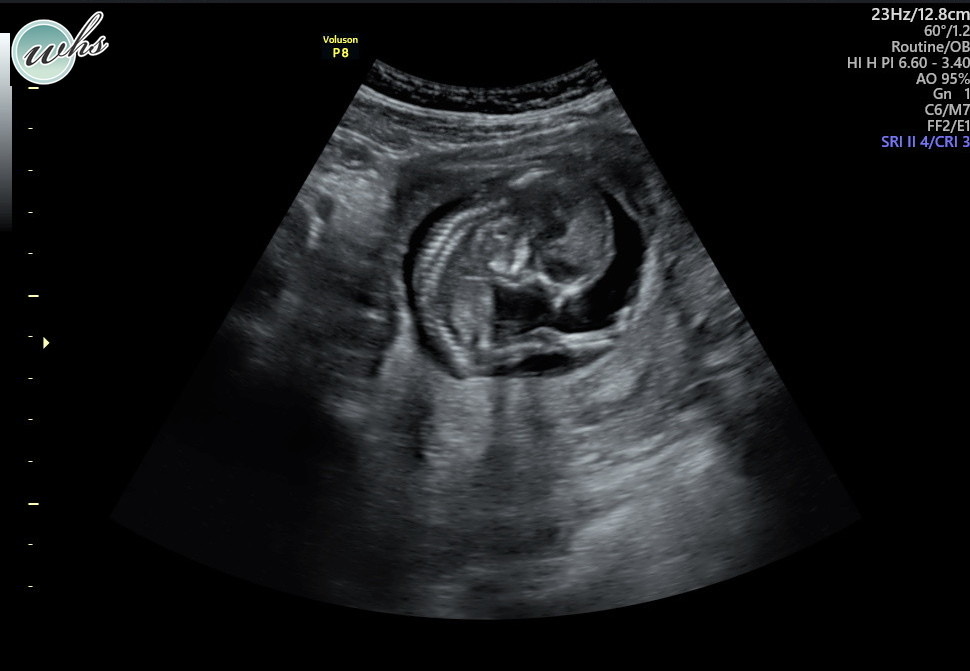

At 14 weeks our ultrasound was perfect! They said the Subchorionic Hematoma had resolved and our daughter was on track. Watching her wiggle around in there was so wonderful. She had quite the personality already.

I will never forget how difficult it was to see our girl on the screen, all squished in there without the fluid needed around her to keep her safe and healthy.

My husband was with me through FaceTime, but he was at home about 20 minutes away. He rushed to me as quickly as he could, and I swear to you time stopped. Time stopped for us while it continued for everyone else in the world around us. Our baby was alive, her heart was beating, she was measuring at 20 weeks… but she had very little fluid around her. Time stopped and tears fell when our OBGYN told us how serious this was and while we waited to see a specialist.

Over the course of the next week and a half we would learn so much. Visits with specialists would initially offer hope… she was perfectly developed and had a small amount of amniotic fluid, but likely not enough. They called it Oligohydramnios. And over time our hope would become less and less… without fluid our daughter would never develop her lungs properly and it was only a matter of time until an infection called Chorioamnionitis could kill both our baby and myself. I was urged to take my temperature several times a day and watch myself closely for signs of infection. For a week and a half I spent most of my time in bed, desperately searching for success stories and any indication that things could still turn out ok. I’d visit Labor and Delivery frequently to check for leaking amniotic fluid, and somehow it was never detected. The only explanation we ever received was that the amniotic sac must’ve been compromised when I had the Subchorionic Hematoma and I had a slow leak over a long period of time. I tried IV fluids, supplements, and drank so much water in effort to help increase the amniotic fluid around her. But every ultrasound became more and more bleak. The fluid was decreasing and she was unable to move. I could feel her hiccup, but she could not move. It’s truly gut wrenching to see your baby this way.